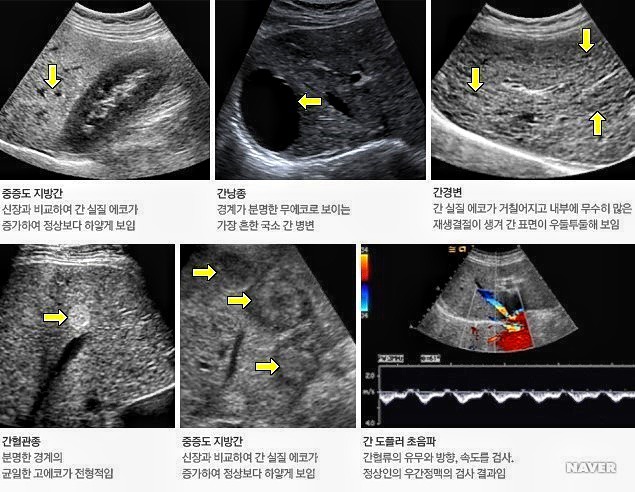

8. 진단질병

지방간, 만성 간질환, 간경화, 담낭/담관 결석, 방광염, 급성 충수염, 자궁근종, 전립선 비대증, 갑상선 결절

1) 간: 간기능 검사 이상 시 일차적 검사, 지방간, 만성 간질환, 간경화의 추적 검사, 간세포암, 간내 담관암, 전이암의 보조 진단,간 이식의 수술 전 및 후 혈류 평가, 간실질 및 간종양의 조직 검사, 간종양의 고주파열 치료

2) 담도 및 담낭: 담낭/담관 결석, 담낭암/담관암의 보조 진단, 담낭염의 진단, 담낭 폴립의 추적 검사

초음파 검사장비

검사결과